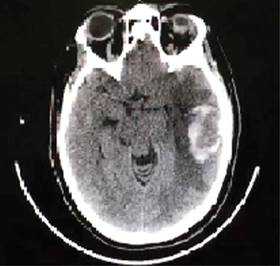

A su ingreso en UCI se recibe paciente bajo intubación orotraqueal y ventilación mecánica invasiva bajo sedación, a su llegada se realiza tomografía de cráneo simple, la cual muestra: hematoma parenquimatoso temporoparietal izquierdo, de 55 × 88 × 50 mm (aproximadamente 38 cm3), edema cerebral, colapso de sistema ventricular lateral ipsilateral y desviación de la línea media 9 mm aproximados (Figura 2), es valorada por neurocirugía, descartándose manejo quirúrgico de urgencia, se inicia terapia osmolar con soluciones hipertónicas al 7.5%, medidas antitrombóticas, y resto de manejo con base en metas internacionales de paciente neurocrítico, manteniendo evolución estacionaria, la nueva tomografía de cráneo cinco días después de su ingreso (Figura 3) muestra infarto cerebral en hemisferio izquierdo y sangrado intraparenquimatoso antiguo, el cual se encuentra en procesos de reabsorción, además de edema cerebral severo, por lo que amerita intervención por neurocirugía, donde se realiza craniectomía parietofrontal izquierda, para mejoría de compliance cerebral. La TAC de control posterior a evento quirúrgico (Figura 4) reporta disminución del edema.

Figura 2: Tomografía computarizada de cráneo con presencia de hematoma parenquimatoso temporoparietal izquierdo, 38 cm3 aproximadamente.